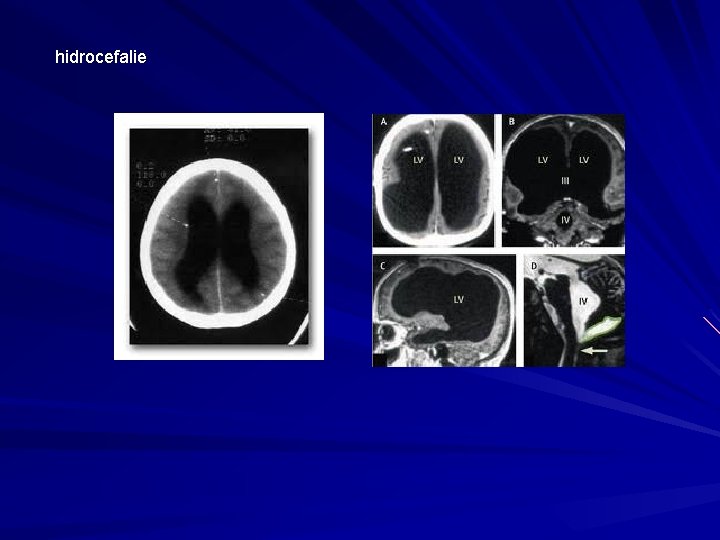

hidrocefalie